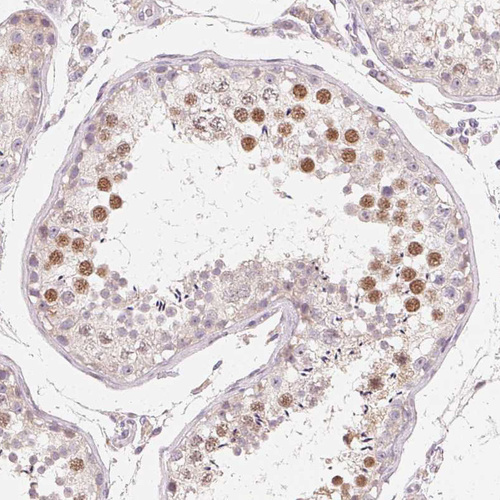

Immunohistochemical staining of human Testis shows moderate nuclear positivity in cells in seminiferous ducts.